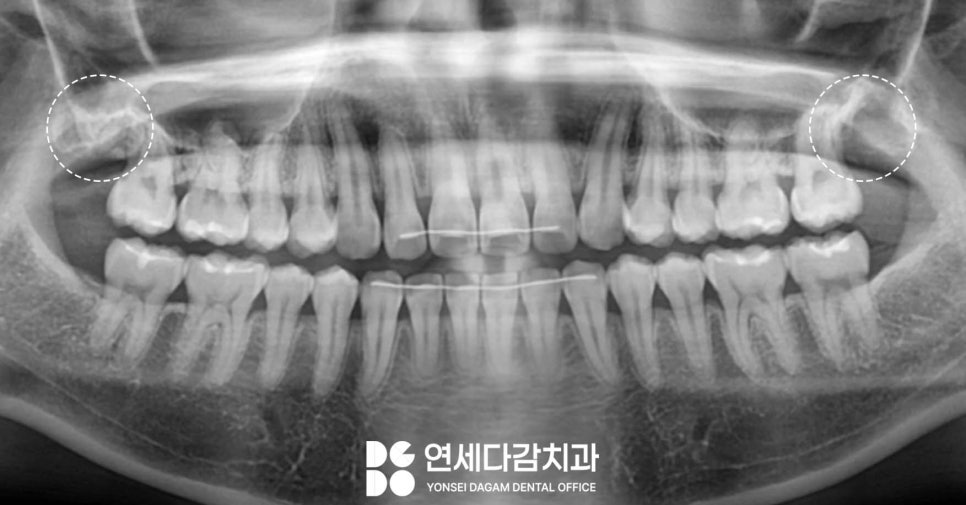

특히 위턱 매복 사랑니 중에서도

인접치 쪽(근심)으로

기울어져 있는 경우에는

개롱역 치과 에서 보여드린 사진처럼

음식물이 자주 끼는 구조가 만들어져

많은 불편감을 느끼게 됩니다.

치관 부분이 앞쪽 어금니를 밀고 있고,

한 번에 제거하기 어려우며,

다른 케이스를 살펴보면

심하게 근심으로 기울어져 있는 곳

(사진 기준 왼쪽)과 아닌 곳이 있습니다.